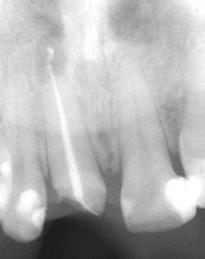

Figures 1A-1B: Two periapical radiographs of tooth No. 24 taken at different angles. Resorptive defect changes position relative to root canal, which according to buccal object rule, means defect is separate from canal and, hence, external to canal

Differential diagnosis

While external root resorption comes in many forms, such as transient surface resorption, pressure resorption, external inflammatory root resorption, invasive cervical root resorption, and replacement resorption (ankylosis), internal root resorption is uniquely different. The differential diagnosis is made by taking multiple radiographs at different angles.9,10 Utilizing the buccal object rule, a lesion of internal origin will remain close to the canal regardless of the angle, while a lesion of external origin will move away from the canal depending on the angle of the radiograph (Figures 1A and 1B).

Additionally, with IRR, the outline of the root canal is usually distorted and appears contiguous with the resorptive defect, while with external resorption, the root canal outline appears normal and can usually be seen running through the radiolucent resorptive defect, as there remains a thin layer of dentin separating the canal from the resorptive area9-10 (Figures 2A-2D).